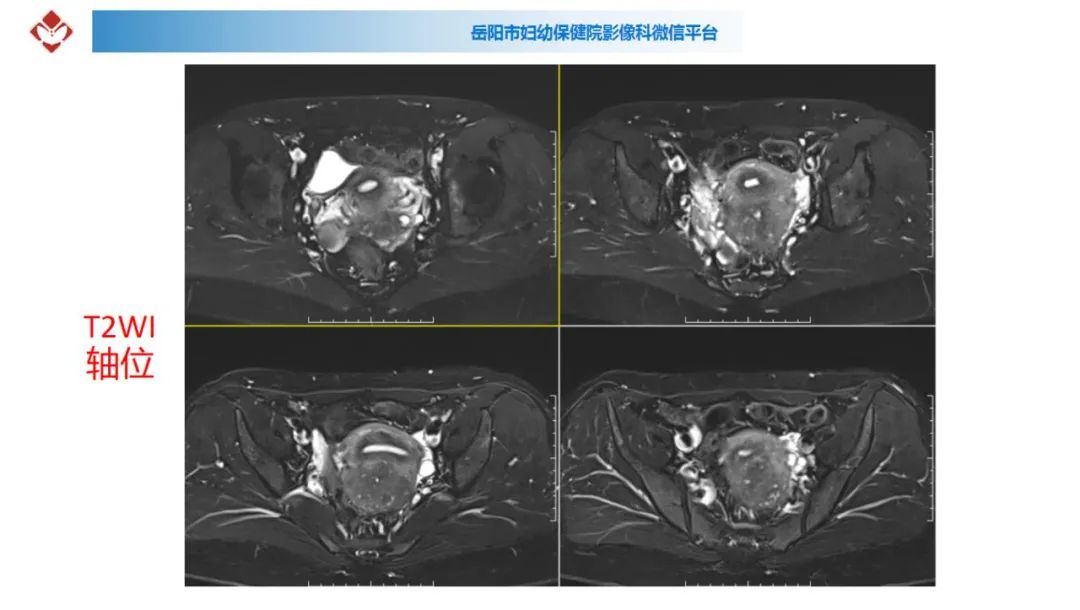

典型疑难病例讨论

来源:岳阳市妇幼保健院影像科